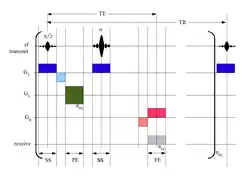

Messsequenz, Ortskodierung, Bildaufbau

Zum besseren Verständnis wird hier das Prinzip der grundlegenden (1950 von Erwin Hahn erfundenen) Spinecho-Sequenz kurz skizziert. Eine „Sequenz“ (auch „Pulssequenz“) ist in diesem Zusammenhang eine Abfolge von Hochfrequenz- und magnetischen Gradientenfeldern (in drei orthogonalen Orientierungen), die vielfach in jeder Sekunde in vorgegebener Reihenfolge ein- und ausgeschaltet werden.

Zu Beginn steht ein resonanter Hochfrequenzimpuls mit der Larmor-Frequenz, der sogenannte π/2- oder 90°-Anregungspuls. Durch diesen wird die Magnetisierung um 90° quer zum äußeren Magnetfeld ausgelenkt. Sie beginnt um die ursprüngliche Achse zu kreisen (zu präzedieren).

Das dabei entstehende Hochfrequenzsignal kann außerhalb des Körpers gemessen werden. Es nimmt exponentiell ab, weil die Protonenspins aus dem „Takt“ geraten („dephasieren“) und sich zunehmend destruktiv überlagern. Ein geeigneter 180°-Rephasierungs-Hochfrequenzimpuls bewirkt, dass ein Teil der Dephasierung (-Dephasierung durch zeitlich unveränderliche Magnetfeldinhomogenitäten) zum Zeitpunkt der Messung wieder rückgängig gemacht wird, so dass wieder mehr Spins in der gleichen Phase sind und ein sogenanntes Spinecho entsteht. Die Signalstärke hängt dann nicht von der -Relaxationszeit ab, sondern nur noch von der -Relaxationszeit, die auf nicht-reversiblen Effekten beruht. Abhängig von den Sequenz-Parametern kann das Signal darüber hinaus auch von der -Relaxationszeit abhängen, die beschreibt, wie sich die ursprüngliche Längsausrichtung der Spins zum äußeren Magnetfeld wieder einstellt.

Um eine -gewichtete Aufnahme zu erhalten, setzt man den Rephasierungsimpuls relativ spät, so dass die Spin-Spin-Relaxation Zeit hat, sich auszuwirken; man spricht von einer langen Echozeit TE (). Auch der zeitliche Abstand bis zur nächsten Messung ist sehr lang, damit die (maximale) longitudinale Ausgangsmagnetisierung durch die Spin-Gitter-Relaxation in allen Geweben weitestgehend wieder erreicht wird. Man spricht von einer langen Repetitionszeit TR (). Mit langer TE und langer TR bekommt man helles Signal nur von Geweben mit langer -Zeit. Für eine -Wichtung braucht man umgekehrt kurze TE () und kurze TR (), dann überwiegen die unterschiedlichen Spin-Gitter-Relaxationen verschiedener Gewebe im Bildkontrast. Eine Sequenz mit kurzer TE () und langer TR () erzeugt einen Kontrast, der sich überwiegend nach der Konzentration der Protonen im Gewebe richtet, die praktisch der Anzahl der Wasserstoffatome entspricht; dies ist die sogenannte Protonendichte-(PD-)-Wichtung. Es gibt zahlreiche Weiterentwicklungen dieser einfachen Spinecho-Sequenzen, etwa zur Beschleunigung oder mit Unterdrückung des Fettgewebesignals. Eine klinische MRT-Untersuchung umfasst unterschiedlich gewichtete Bildserien und mehrere räumlichen Ebenen.

Um aus den Signalen ein Bild zu berechnen, also die Signale den einzelnen Volumenelementen (Voxeln) zuzuordnen, wird mit linear ortsabhängigen Magnetfeldern (Gradientenfeldern) eine Ortskodierung erzeugt. Dabei wird ausgenutzt, dass für ein bestimmtes Teilchen die Larmorfrequenz von der magnetischen Flussdichte abhängt (, je stärker das Magnetfeld entlang der Präzessionsachse, desto höher die Larmorfrequenz). Die Gradientenfelder werden in drei orthogonalen Orientierungen angewendet; diese Richtungen beziehen sich auf die Änderung der Magnetfeldstärke, die Magnetfeldrichtung bleibt dabei immer parallel zum externen Magnetfeld :

- Ein Gradient liegt während der Anregung an, so dass nur eine einzelne Schicht des Körpers die zum Anregungspuls passende (resonante) Larmorfrequenz besitzt, also nur die Spins dieser Schicht ausgelenkt werden (Schichtselektionsgradient).

- Ein zweiter Gradient senkrecht zum ersten (beispielsweise entlang der zu rekonstruierenden Bildzeilen) wird nach der Anregung kurz eingeschaltet und bewirkt eine kontrollierte Dephasierung der Spins. Die Spins in jeder Bildzeile präzedieren für die Dauer des Gradienten unterschiedlich schnell, was das Summensignal (nach dem Gradienten) schwächt (Phasenkodiergradient). Diese Messung wird mit inkrementell veränderter Gradientenstärke so oft wiederholt, wie Bildzeilen berechnet werden sollen.

- Der dritte Gradient wird während der Signalaufnahme (Messung des Spinechos) rechtwinklig zu den beiden anderen geschaltet; er sorgt dafür, dass die Spins jeder Bildspalte während der Auslese eine andere Präzessionsgeschwindigkeit haben, also eine andere Larmorfrequenz senden (Auslesegradient, Frequenzkodiergradient).

Alle drei Gradienten zusammen bewirken, dass das empfangene Signal zu einer bestimmten Schicht des Körpers gehört und (für jeden Zeitpunkt der Auslese und jede Wiederholung/Repetition) eine Kombination aus Frequenz- und Phasenkodierung enthält. Die Messungen werden zeilenweise in eine Matrix („k-Raum“) eingetragen. Der k-Raum enthält in jedem Punkt also das Summensignal aller Spins der Bildschicht mit ortsabhängiger Dephasierung. Die Achsen des k-Raums entsprechen horizontalen und vertikalen Ortsfrequenzen; die Punkte im k-Raum den Wellenvektoren. Mit einer zweidimensionalen Fourier-Transformation wird aus der k-Raum-Matrix das zugehörige Bild im Ortsraum berechnet, d. h. für jedes Voxel die Signalstärke ermittelt, indem die Beiträge der einzelnen Frequenzen getrennt werden.